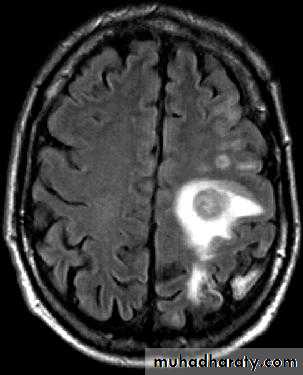

Brain Abscess MRI

د.عبدالرحمن

• B. Radiological Investigations:

• CT or MRI is the investigation of choice.

• CT Brain is performed with and without contrast.

• MRI is done with gadolinium enhancement.

• They will show a single (or multiple) space occupying lesion that is well delineated with an enhancing wall, with variable surrounding oedema.

• The differential diagnosis of a single brain abscess in CT or MRI is a solitary metastasis, primary brain tumour or cerebral infarction.

• The differential diagnosis of multiple brain abscesses is from multiple metastasis and tuberculoma.